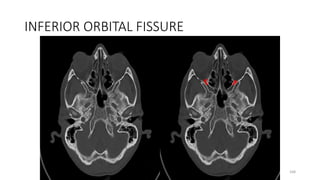

Inferior orbital fissure